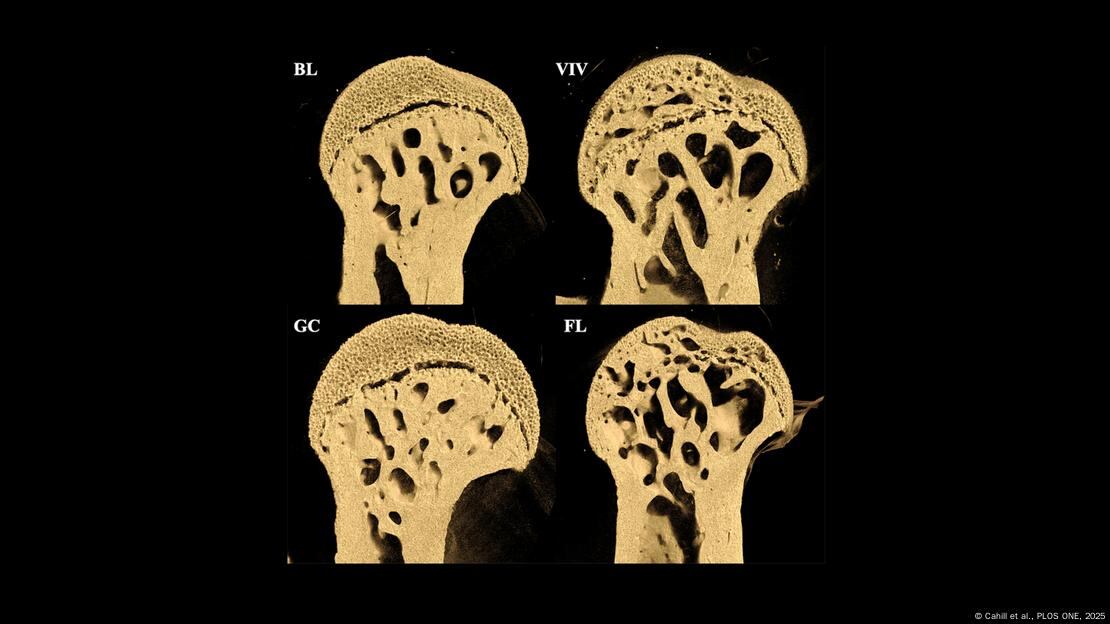

Los resultados sorprendieron incluso a los propios investigadores: los fémures de los ratones que viajaron al espacio estaban “plagados de grandes agujeros”, según reportó Science Alert, y presentaban un daño visible en los extremos que conectan con la cadera y la rodilla.

“Uno de los focos específicos de nuestro estudio es el fémur, debido a su importante función de soporte de peso en el ratón”, detallaron los científicos.

En contraste, huesos como los de la región lumbar de la columna vertebral – sin función significativa de soporte en estos animales – no mostraron degradación alguna, lo que indica que la pérdida ósea no es uniforme, sino que afecta especialmente a las estructuras sometidas a carga en la Tierra.